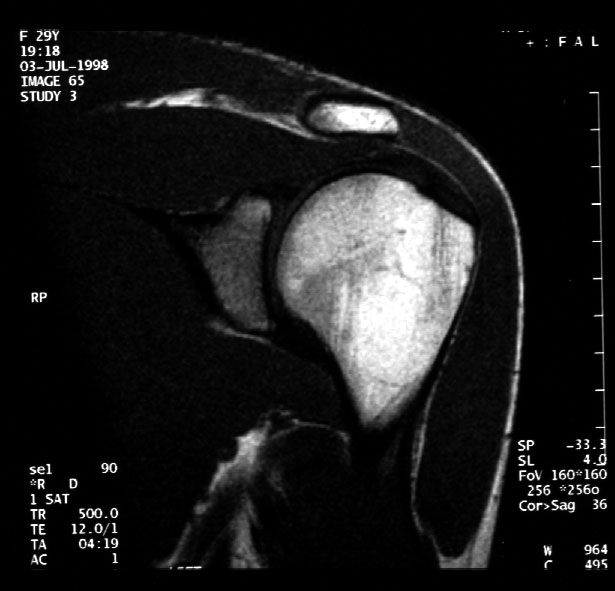

Normal MR of Left Shoulder (coronal) -- Identify: humeral head, acromion,

glenoid, deltoid,muscle, supraspinatus muscle, subscapularis muscle